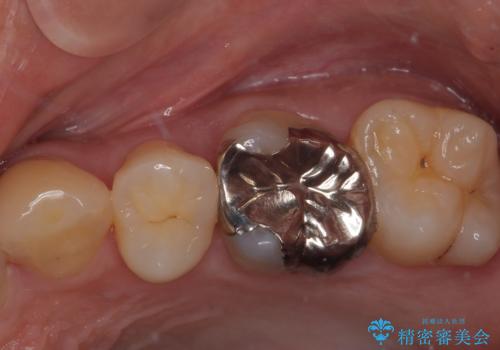

右下の銀歯が外れた オールセラミッククラウン

担当医 有澤哲郎